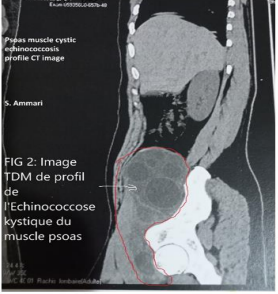

A 29-year-old patient, with no history of disease, consulted for right iliac fossa (RIF) and right thigh root pain, evolving for two weeks. The clinical examination finds a patient in good general condition, apyretic, body mass index (BMI) at 25. Visible and palpable oblong mass occupying right flank, the RIF, and the root of the right thigh; it was firm, painless, adherent to the deep plane, extended on about 20 cm of long axis. There’s a limitation in the extension of the right thigh in relation to psoitis. Digital rectal exam was without anomalies, hernial orifices were free. Abdominal ultrasound showed a multicystic mass of the right iliac psoas muscle, compressive, evoking cystic echinococcosis. Abdominopelvian computed tomography (CT-scann) found a multi-loculate formation, with a bi-sac wall, of the right pelvic retroperitoneum, contained a central calcification, measuring 22.2 cm high by 9.9 cm x 9.5 cm of transverse axis, extending from the retrocecal region to the root of the right thigh through the crural orifice.

Figure 4: Psoas muscle cystic echinococcosis profile CT image.